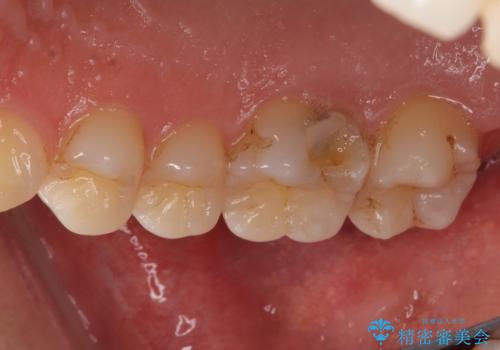

PGA(ゴールド)インレー しみる歯の治療